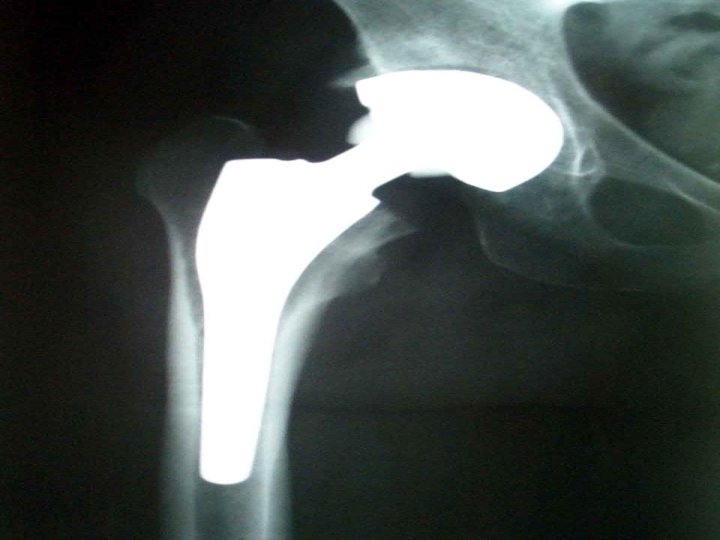

Radiografia Articulações sacroilíacas Coluna vertebral Esclerose óssea perto das superfícies articuladas com anquilose. Erosões nas facetas articulares, ossificação nos corpos, e a coluna adquire a forma de bambu.